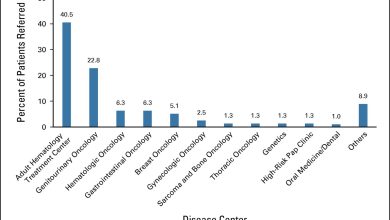

Os serviços de diagnóstico de câncer em um centro de saúde comunitário aceleram o diagnóstico para populações carentes

Encaminhamentos do centro de doenças para o centro de câncer. Crédito: Prática de Oncologia JCO (2023). DOI: 10.1200/OP.22.00487 Um modelo…